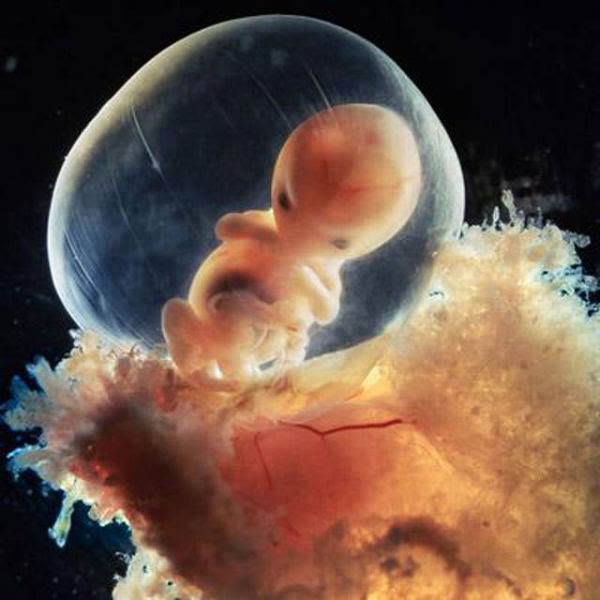

Le fotografie descrivono proprio tutto. Si parte dall’incontro tra ovulo e spermatozoo e il suo ingresso, la fase della blastocisti, che avviene dopo 5 giorni, e si passa a vedere l’embrione che inizia il suo sviluppo nell’utero.

Nilsson ha poi ripreso le prime fasi di sviluppo del cervello, del cuore (che avviene verso il ventiquattresimo giorno), e, alla quinta settimana, il crearsi delle fessure che diventeranno gli occhi, la bocca e le orecchie. Dopo 40 giorni viene documentato il formarsi della placenta, che permette all’embrione di ricevere il nutrimento necessario.